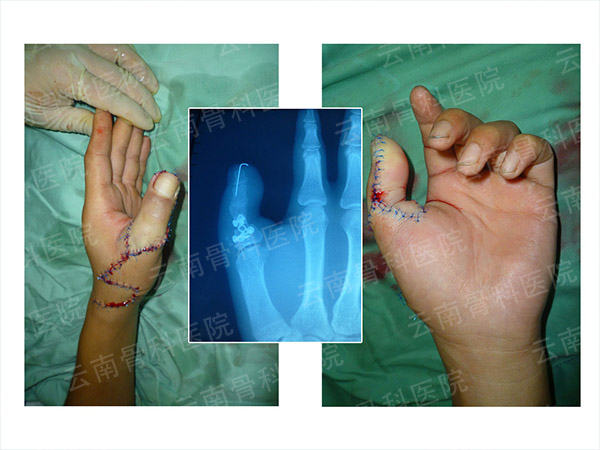

拇指Ⅱ度再造

拇指Ⅲ度再造